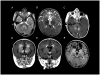

Alexander disease (AxD) is a usually fatal astrogliopathy primarily caused by mutations in the gene encoding glial fibrillary acidic protein (GFAP), an intermediate filament protein expressed in astrocytes. We describe three patients with unique characteristics, and whose mutations have implications for AxD diagnosis and studies of intermediate filaments. Patient 1 is the first reported case with a noncoding mutation. The patient has a splice site change producing an in-frame deletion of exon 4 in about 10% of the transcripts. Patient 2 has an insertion and deletion at the extreme end of the coding region, resulting in a short frameshift. In addition, the mutation was found in buccal DNA but not in blood DNA, making this patient the first reported chimera. Patient 3 has a single-base deletion near the C-terminal end of the protein, producing a short frameshift. These findings recommend inclusion of intronic splice site regions in genetic testing for AxD, indicate that alteration of only a small fraction of GFAP can produce disease, and provide caution against tagging intermediate filaments at their C-terminal end for cell biological investigations.